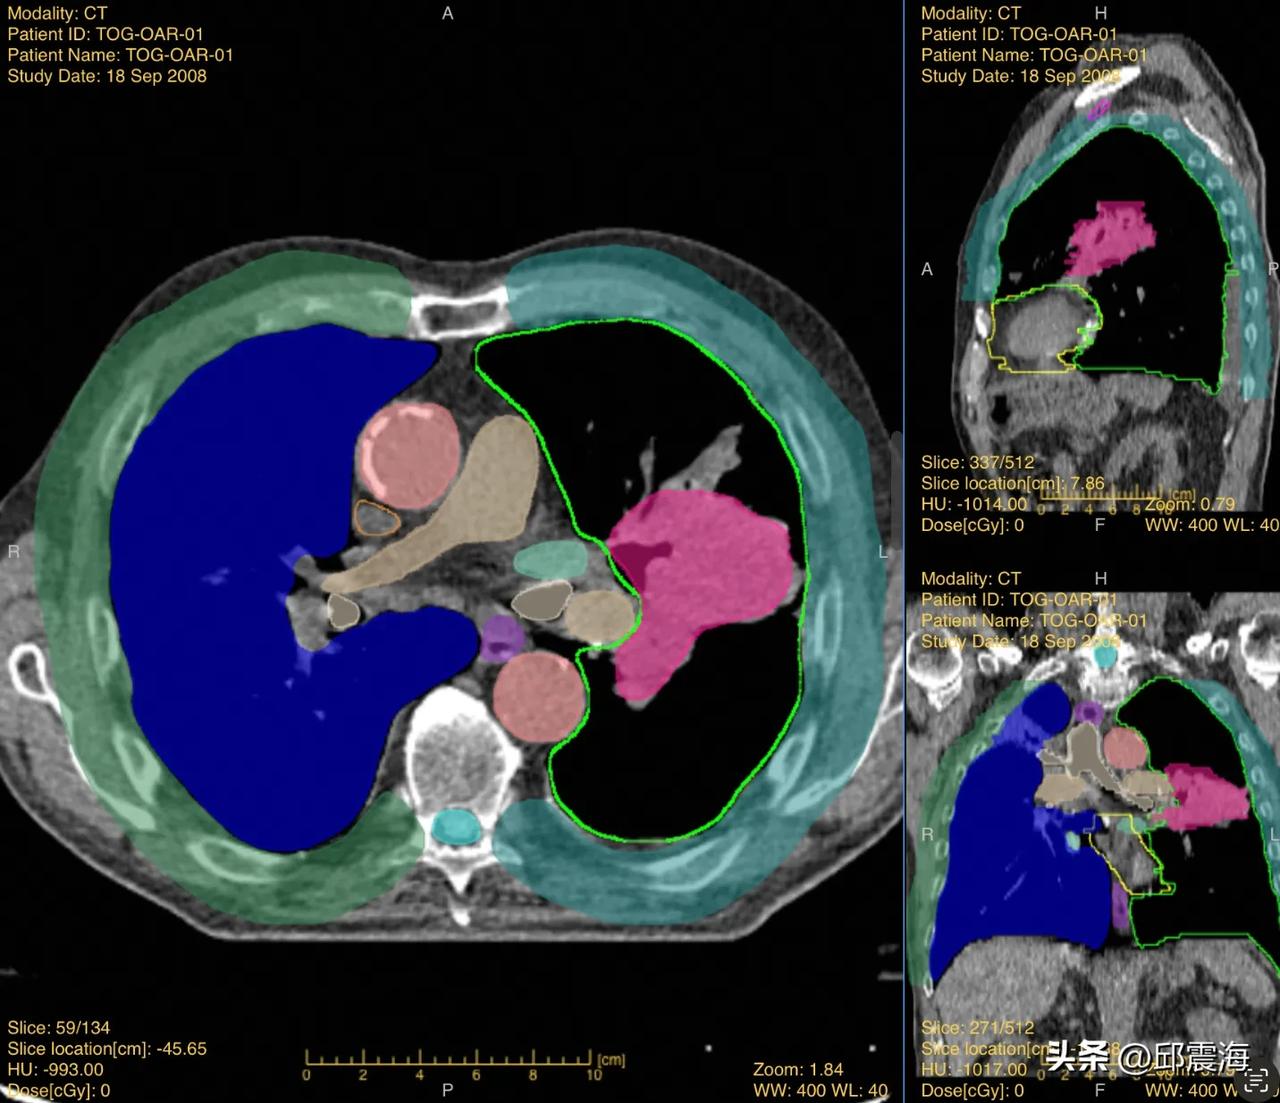

在你不知道的地方,中国科技的有生力量正在壮大、崛起! 最近,达摩院青橙奖获奖名单公布,把15位杰出的年轻科学家推向世界学术舞台,他们平均年龄只有33岁,已经拿出了很多个“世界首个”“国际一流”的研究成果,可以说是中国科研界最优秀的一批年轻力量。 对基础科研的支持,从来不是嘴上声援几句就好了。连续6年,达摩院一直投入真金白银支持年轻科学家搞研究,每年花几千万发掘35岁以下的高潜力科研人才。可见达摩院的愿景从来不是当下的利益,而是成为一家面向未来、以科技解决重大社会问题的企业研究机构。 一边支持基础科研,一边坚持自主研发。 举个例子,胰腺癌因为确诊难,死亡率高,在医学界被称为“癌中之王”。但和所有的癌症一样,胰腺癌发现越早,治愈几率越大,没有有效的大规划筛查手段,是胰腺癌治疗的最大绊脚石。前不久,达摩院拉着全球10多家顶尖医疗机构,研发出胰腺癌早期筛查医疗AI,首次证实了通过“平扫CT+AI”技术,是大规模检测早期胰腺癌的有效手段,学术上成果登上国际顶刊《Nature Medicine》,连罗振宇老师都在2024跨年演讲中特别提及。 客观说,达摩院一直都是在做实事,只要它一直重视科技、坚持用科技解决问题,就是功德无量。我也相信在达摩院的表率下,更多企业将参与到“科技长线投资之中”,届时,会有更多中国本土的青年才俊涌现,支撑着我们的科技实力高质量发展!